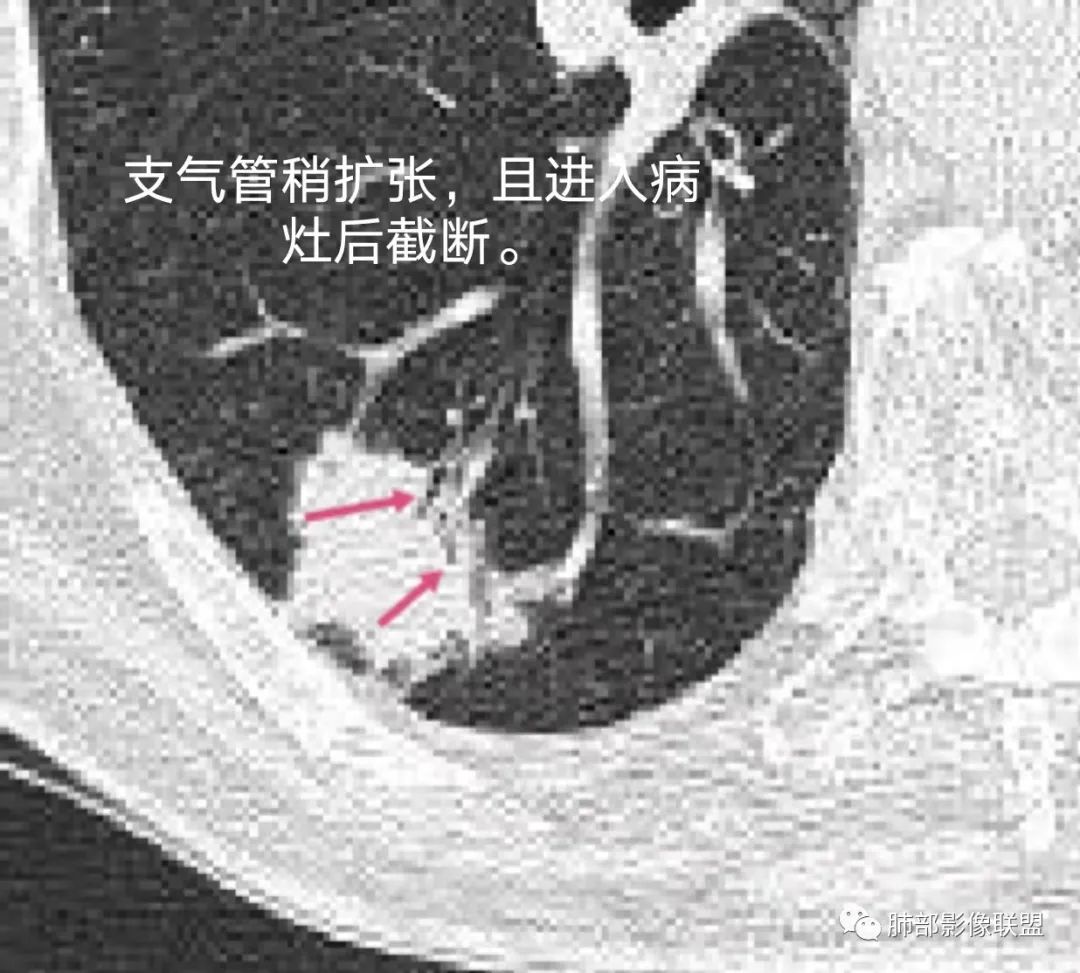

老年男性,右肺下叶胸膜下结节,边缘见清晰磨玻璃密度影及少许索条,支气管进入后截断,周围血管弯,考虑腺癌,鉴别隐球菌

右肺下叶胸膜下混合密度结节,分叶、毛刺,磨玻璃边界尚清晰,血管集束,支气管进入阻断,考虑腺癌

右肺下叶背段胸膜下肿块,边缘不规则,分叶,毛刺,有磨玻璃,边界清,近肺门侧见血管聚集,支气管进入后闭塞,右肺下叶肺静脉牵拉扭曲。诊断,支持腺癌

结节型粘液腺癌,具有血管弯,支气管截断,磨玻璃边界清楚等恶性征象,同时磨玻璃内部较糊,似清非清,不符合普通腺癌附壁生长特点,更像局限的粘液成分。收缩力不强,胸膜局部微积液,内部小空洞(考虑局部粘液排除形成),所以考虑结节型粘液腺癌。

区别1:结节期(影像说结节型)粘液腺癌,粘液成分还大多数局限于粘液腺癌细胞的胞浆中,没有飘出去,所以粘液密度不明显,周围的磨玻璃成分大多数还是分散于肺泡壁上的粘液腺癌细胞,所以边界相对较清楚(时间越晚,飘出去的粘液越多,边界就会越不清楚了),因为胞浆中的粘液成分显得较糊,有点似清非清。而普通腺癌附壁生长的腺癌细胞胞浆中没有粘液,所以非常清楚。

4.原发性肺粘液腺癌侵袭力相对较低,发展慢;病灶较少破坏支气管及血管,可表现为血管造影征及空气支气管征。较少胸膜侵犯,也较少肺门纵隔淋巴结转移。

4.病灶内气管、血管破坏不明显,可出现血管造影征及空气支气管征;也提示病灶侵袭力较低。